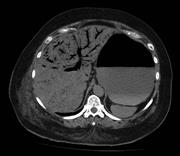

Extensive portal venous gas in a post-operative patient with no identifiable cause

Adam Hussein and Rohit Makhija

Journal of Surgical Case Reports, Volume 2015, Issue 10, October 2015, rjv136, https://doi.org/10.1093/jscr/rjv136